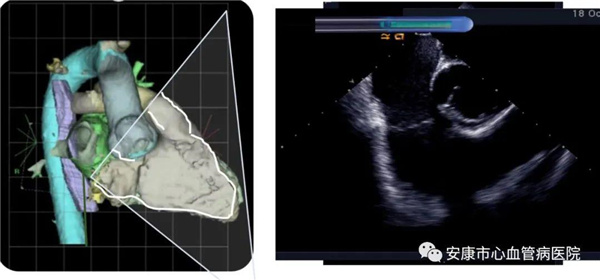

心律失常團(tuán)隊(duì)在11月6日為患者在ICE引導(dǎo)下行房撲射頻消融術(shù)。穿刺左鎖骨下靜脈,導(dǎo)絲走行證實(shí)了合并永存左上腔靜脈。穿刺右股靜脈,分別送入心腔內(nèi)超聲導(dǎo)管和消融電極,超聲下建立右心室、右心房、左心室、左心房、二尖瓣和三尖瓣及三尖瓣峽部模型。ICE就像術(shù)者多了一雙天眼,可以對(duì)心臟內(nèi)部結(jié)構(gòu)一目了然,360度無死角觀察心臟結(jié)構(gòu),可以做到“所視即所及”。建模后,消融三尖部峽部,房撲很快終止,轉(zhuǎn)為竇性心律,手術(shù)獲得成功!手術(shù)用時(shí)僅70分鐘,術(shù)后病情穩(wěn)定,安全返回病房。

心腔內(nèi)超聲(Intracardiac Echocaiography ICE)是將微型的換能器安裝在心導(dǎo)管的尖端,再經(jīng)外周血管(動(dòng)脈或靜脈)送至心腔,換能器發(fā)射聲波,然后將接受到的回波經(jīng)計(jì)算機(jī)處理后形成超聲圖像。由于換能器放置在心腔內(nèi),不受空氣等因素的干擾,因此比經(jīng)食道超聲檢查圖像更加清晰,可以辨別心內(nèi)的細(xì)微結(jié)構(gòu),臨床上主要用于指導(dǎo)心律失常的射頻消融治療。

ICE不僅能檢查左心耳結(jié)構(gòu)、指導(dǎo)房間隔穿刺,而且能精確構(gòu)建左房及肺靜脈解剖結(jié)構(gòu),量化前庭部位與肺靜脈口部的距離,精準(zhǔn)的消融一些復(fù)雜心律失常病例;并且能精確構(gòu)建食道,量化食道與后壁的距離,降低食道損傷幾率;術(shù)中動(dòng)態(tài)監(jiān)測(cè)積液變化,實(shí)時(shí)監(jiān)測(cè)并發(fā)癥,早發(fā)現(xiàn)早處理。因此心腔內(nèi)超聲真可謂是房顫射頻消融手術(shù)安全保障的一只“天眼”。此外這只“天眼”現(xiàn)在還應(yīng)用于心臟瓣膜手術(shù)、起搏器植入等心臟介入手術(shù)。